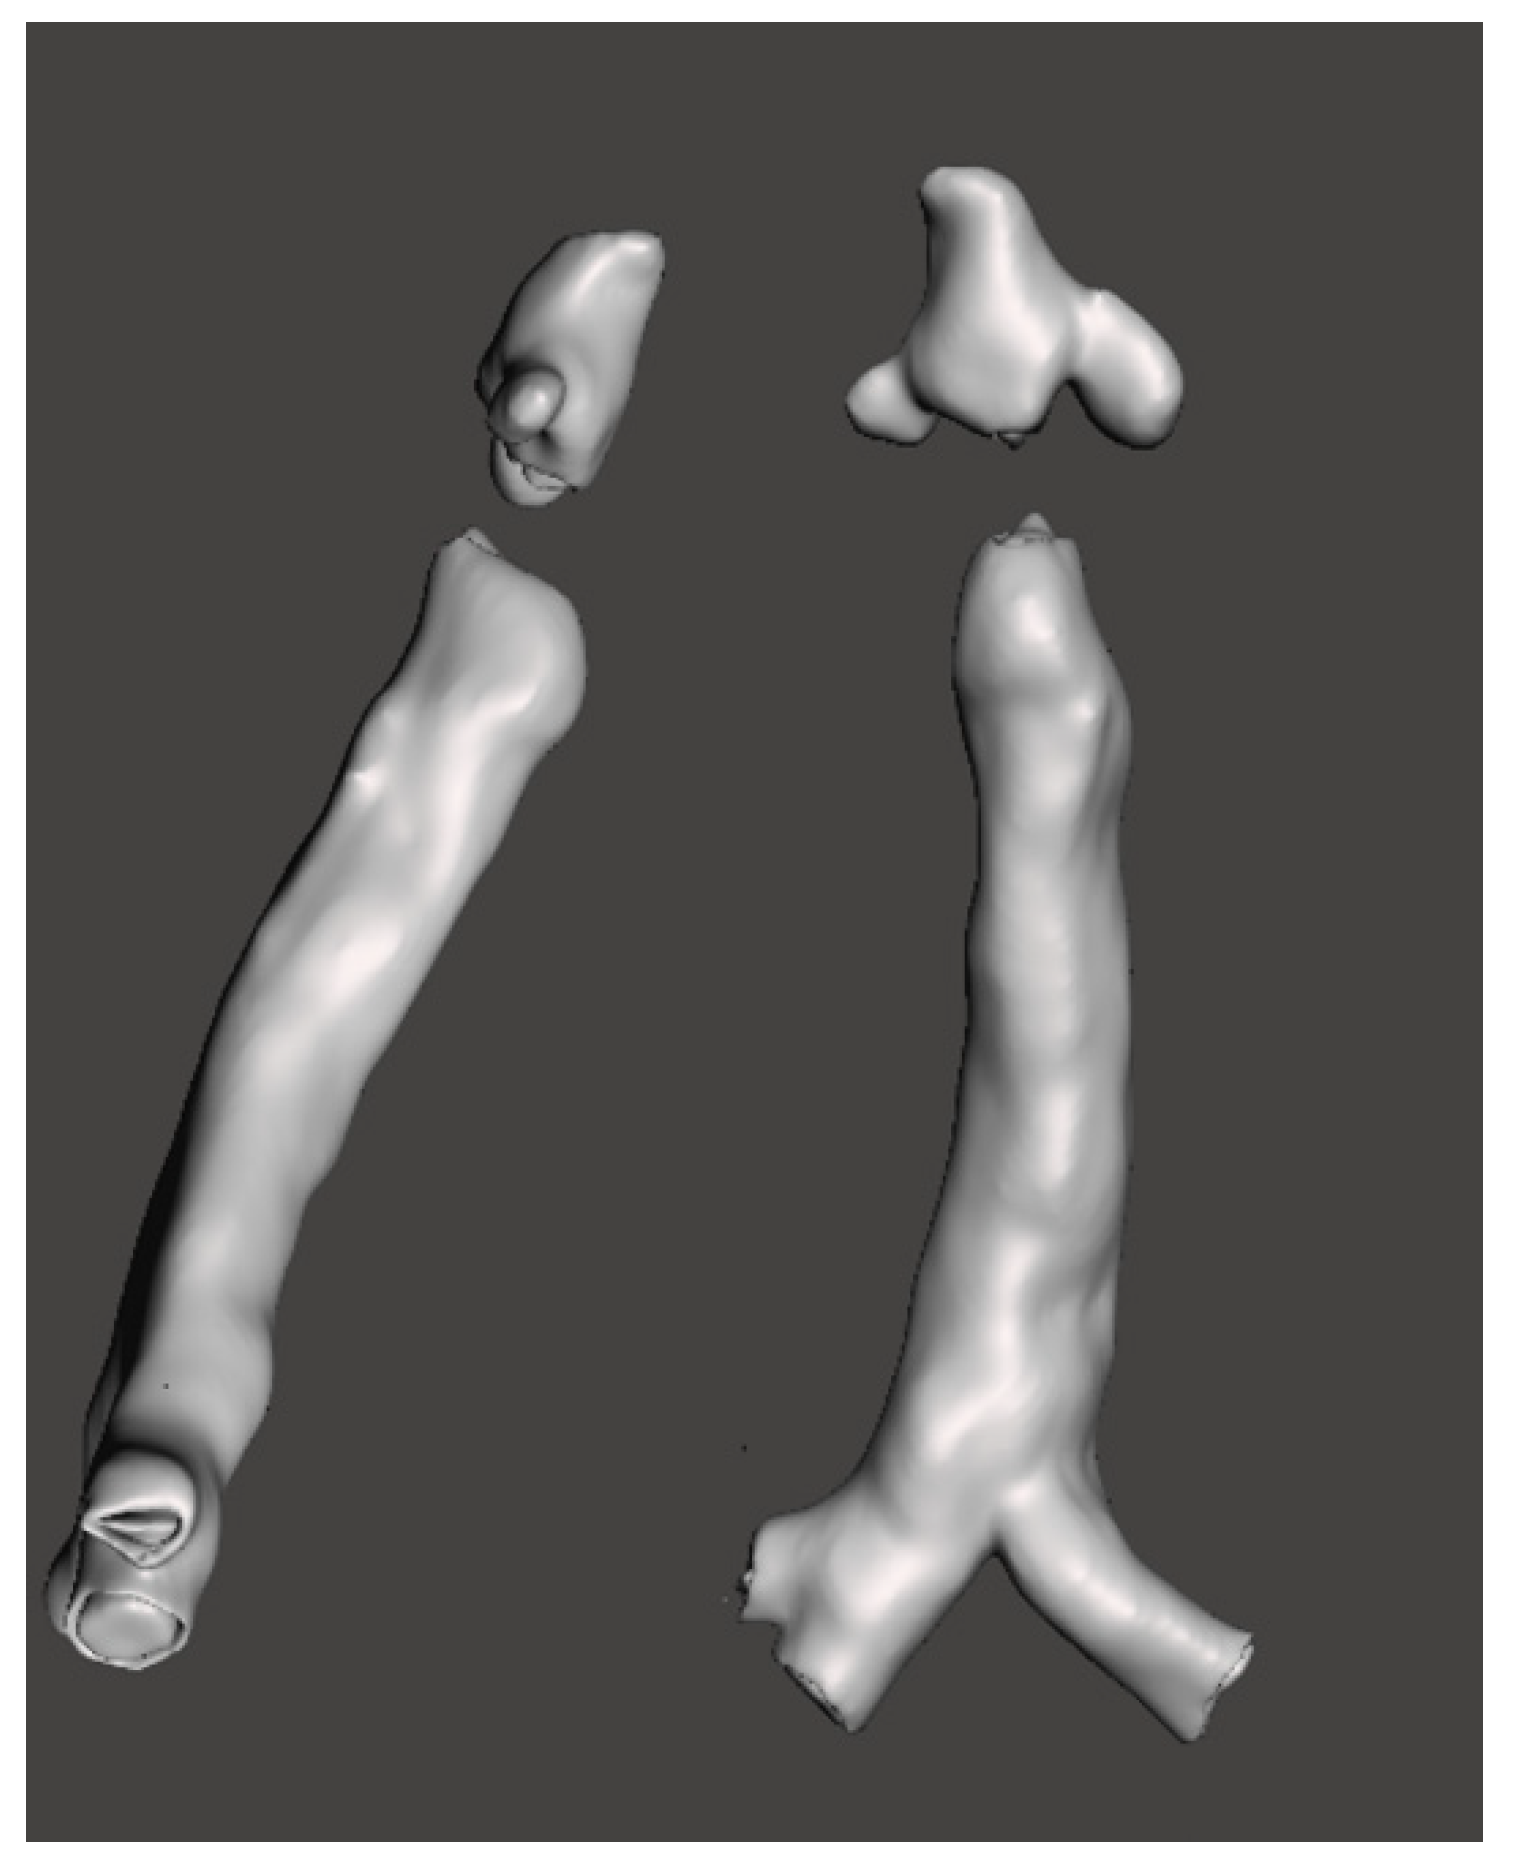

3.3. 3-Dimensional Reconstruction (3D) and Virtual Endoscopy (VE)